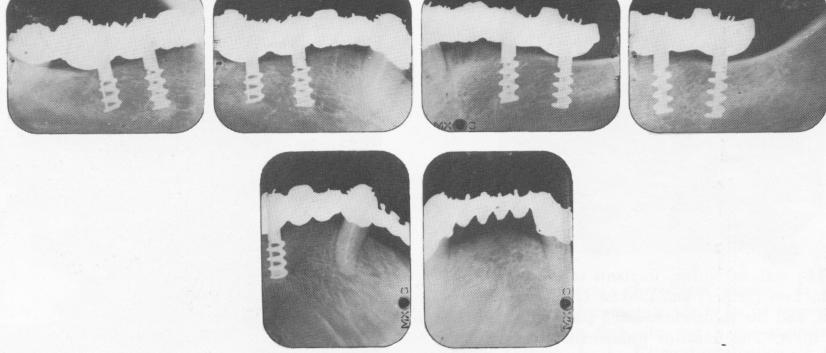

Fig. 5-41. Muratori's early implant inserted by Linkow. Bone regrowth is good, and the x-rays afford a better idea of how the spiral is wound around the vertical struts.

1 Muratori`s early endosseous implant inserted by Linkow in mandible

of a spiral encircling two narrow vertical uprights and surmounted by an internally threaded shaft (Fig. 5-40). This latter part was much too bulky and, being the same diameter as the spiral part, invited tissue breakdown and soft tissue invagination. Even with this drawback, success was possible (Fig. 5-41).